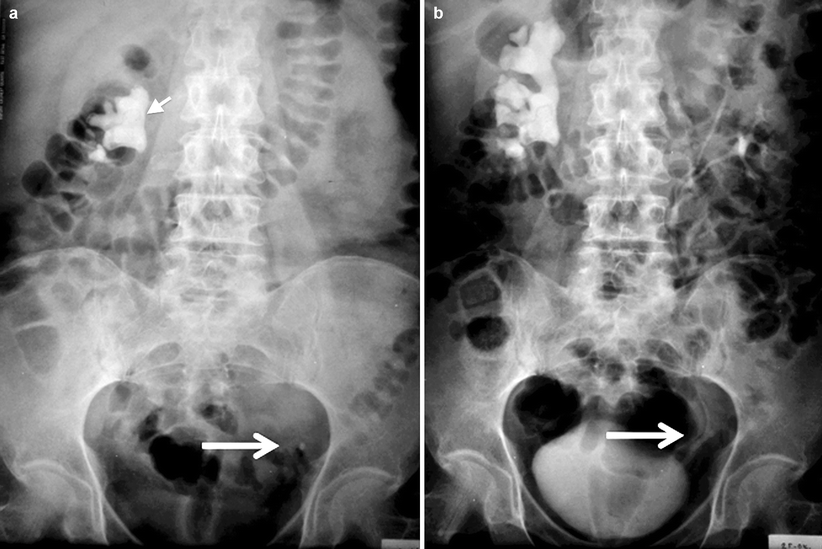

Horse shoe kidney. (A) Intravenous urography shows medialization of the

Horse shoe kidney. (A) Intravenous urography shows medialization of the Horseshoe Kidney With Renal Calculus Icd 10 N20.0 is a billable diagnosis code used to specify a medical diagnosis of calculus of kidney. The 2025 edition of icd. Crystals in the pelvis of the kidney. Condition marked by the presence of renal calculi, abnormal concretions within the kidney, usually of mineral salts. Cake kidney, congenital fusion of kidneys,. Q63.8 is a billable diagnosis code used to specify. Horseshoe Kidney With Renal Calculus Icd 10.